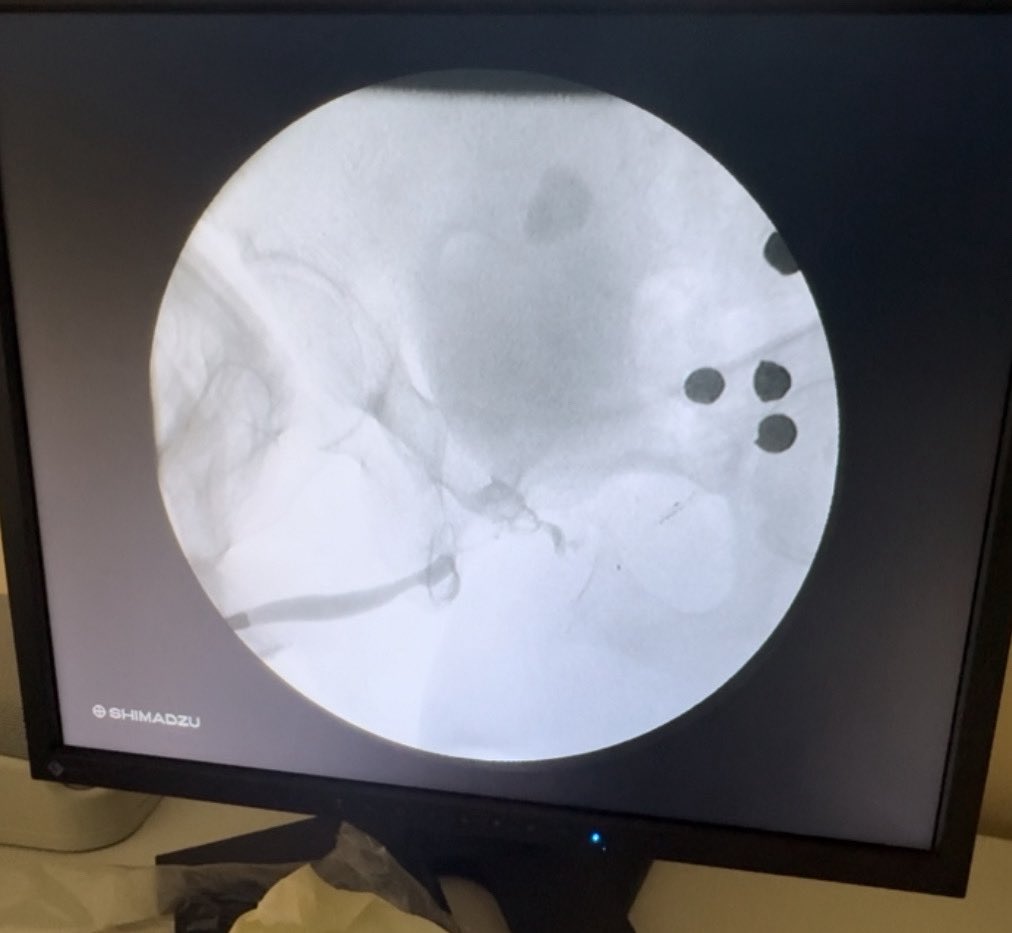

It's an old technique but once you don't have enough urethra to anastomose or augment, pedicled penile skin flap-tube might be the best option left. We also did hyperbaric oxygen therapy (HBOT), which probably helped a-lot. Mark (Toto) Abalajon MD #redourethroplasty #Pedicledskinflap

It's an old technique but once you don't have enough urethra to anastomose or augment, pedicled penile skin flap-tube might be the best option left. We also did hyperbaric oxygen therapy (HBOT), which probably helped a-lot. <a href="/abalajontoto/">Mark (Toto) Abalajon MD</a> #redourethroplasty #Pedicledskinflap